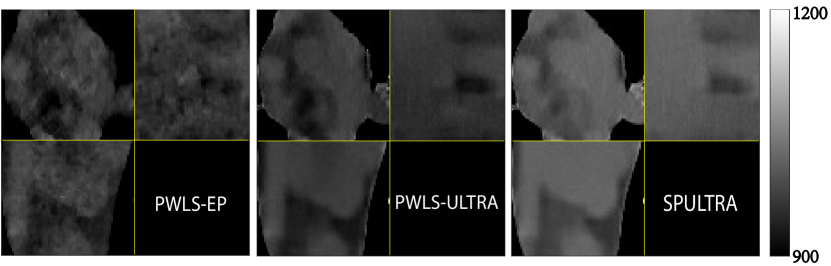

Fig. 4 shows the reconstructed images and the corresponding error images for PWLS-EP, PWLS-ULTRA, and SPULTRA, at and . Compared to the PWLS-EP result, both PWLS-ULTRA and SPULTRA achieved significant improvements in image quality in terms of sharper reconstructions of anatomical structures such as bones and soft tissues, and suppressing the noise. However, the PWLS-ULTRA method introduces bias in the reconstructions, which leads to larger reconstruction errors compared to the proposed SPULTRA method. In Fig. 4, we marked three 3D ROIs in the axial plane, i.e., ROI 1, ROI 2, and ROI 3. Fig. 5 shows the zoom-in images of a 3D plot of ROI 1, and those of ROI 2 and ROI 3 are shown in the supplement. We also plot the evolution of RMSE through the axial slices of the three 3D ROIs in Fig. 6. The figures demonstrate that SPULTRA clearly outperforms the competing PWLS-EP and PWLS-ULTRA schemes.

The above advantages of SPULTRA can be seen more clearly when observing the image profiles. Fig. 7 plots the image profiles for the three methods together with that of the ground-truth image. Fig. 4 shows the horizontal green solid line and the vertical red dashed line, whose intensities are plotted in Fig. 7. It is obvious that the profiles for SPULTRA are closest to the ground-truth among the three compared methods. The gap between the profiles of the PWLS-based methods and the ground-truth shows the bias caused by the compared PWLS methods.

VIII-C Zoom-ins of ROI 2 and ROI 3 in the XCAT phantom simulations

Fig. 14 and Fig. 15 plot the zoom-ins and the corresponding error images of ROI 2 and ROI 3 for the XCAT phantom simulations in Section V.A, with and , respectively. In Fig. 15, we highlighted a region in the axial slice with small red arrows. We show the zoom-ins of the ground-truth ROI 2 and ROI 3 of the XCAT phantom in Fig. 16. The results show that SPULTRA improves image quality over PWLS-EP and PWLS-ULTRA by reducing bias and improving image edges.